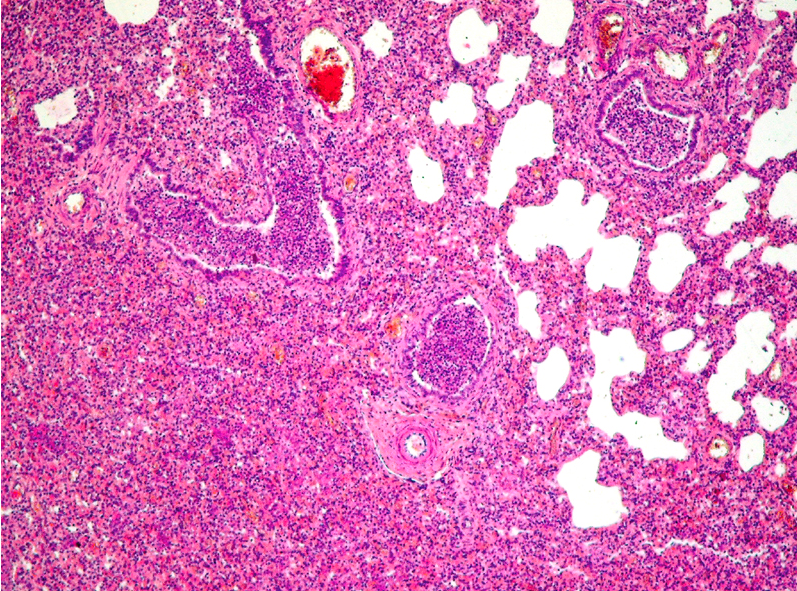

Identify Lesion

What is the cause?

Bronchopneumonia

Caused by infection of air way (trachea, bronchi)

Streptococci, staphylococci

Causes: Patients with long term diseases